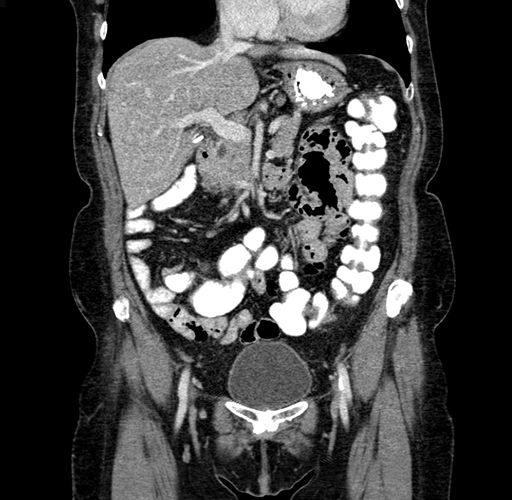

Coronal Venous